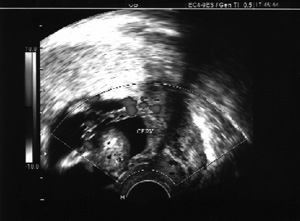

Εικόνα 1: Υπερπλασία ενδομητρίου. Εικόνα 2: Κύηση 13 εβδoμάδος. Αποκόλληση πλακούντα.

ΙΣΤΟΡΙΚΟ

Πρόκειται περί ασθενούς ηλικίας 42 ετών και τεταρτοτόκου (2 ΦΤ, 1 ΚΤ). Η προηγούμενη κύηση συνοδεύονταν με ενδομήτρια καθυστέρηση ανάπτυξης του εμβρύου, το οποίο γεννήθηκε με καισαρική τομή στη 36η εβδομάδα και είχε βάρος 1700 γρ. Στο ιστορικό της ασθενούς αναφέρονται 5 τεχνητές εκτρώσεις και 1 αυτόματη και χρήση καπνού 30 τσιγάρα ημερησίως. Η ασθενής απευθύνθηκε σε γυναικολόγο αιτιόμενη διαταραχές της περιόδου (σταγονοειδής αιμόρροια, μεγάλα διαστήματα αμηνόρροιας, εξάψεις, καταβολή δυνάμεων και ανησυχία). Η τελευταία κανονική περίοδος ήταν στις 10/01/02. Υποβλήθηκε δε σε πολλούς υπερηχογραφικούς ελέγχους της ελάσσονος πυέλου από τους οποίους ο πρώτος -κολπικός- υπέρηχος ( 07/03/02) έδειξε ευρήματα συμβατά με υπερπλασία του ενδομητρίου. Επίσης διαπιστώθηκε κύστη του δεξιού εξαρτήματος διαμέτρου 3 εκ. , καθώς και πεπαχυσμένο ενδομήτριο πάχους 13 χιλ. (εικ. 1).